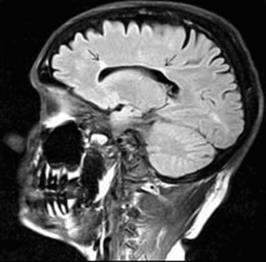

The T2 hyperintense plaque is the characteristic MRI finding of demyelination secondary to MS (Figure 22.1). Plaques are generally easier to visualize by FLAIR, a sequence in which the bright CSF signal is removed. Common plaque locations are in the periventricular white matter, corpus callosum, centrum semiovale, and middle cerebellar peduncle. Although plaques may have a variety of appearances, those that are ovoid in shape are most suggestive of MS. Lesions in the corpus callosum that are oriented perpendicularly to the lateral ventricles are known as Dawson’s fingers (Figure 22.2) and are particularly characteristic of MS. These lesions are best visualized using FLAIR sequences in the sagittal plane. Plaques may accompany both new and old (presumably inactive) MS symptoms.

Figure 22.2 Sagittal FLAIR MRI showing Dawson’s fingers (arrows): two periventricular plaques oriented perpendicularly to the lateral ventricles, a finding highly characteristic of MS.